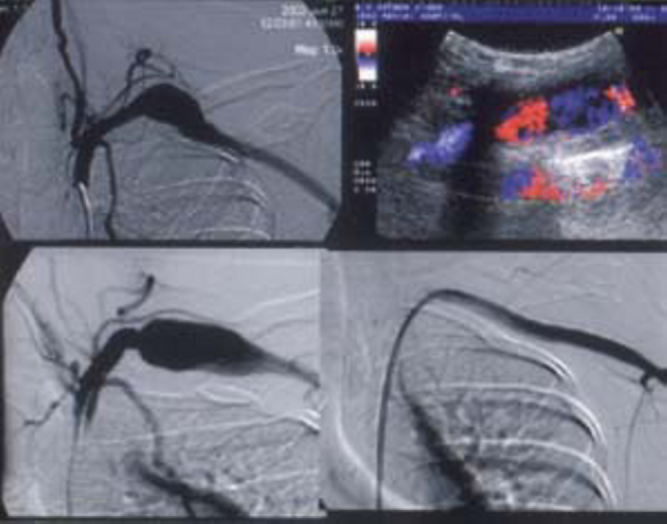

Fig. 2B.

Stent graft treatment of subclavian artery pseudoaneurysm. At left are DSA images showing an increase in pseudoaneurysm size. At right a color doppler image shows turbulence within pseudoaneurysm. DSA images display flow across the stent graft and isolation of pseudoaneurysm with adequate distal run off.